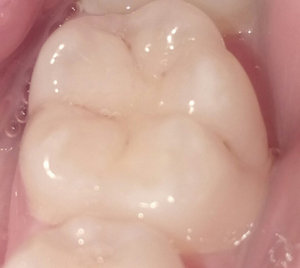

Второй вопрос: Мне вылечили от кариеса семнадцатый и двадцать шестой зубы. Лечение производилось от двух до трех недель назад. До этого жевать было удобно, как твердую, так и мягкую пищу. Сейчас есть мягкую пищу удобно и комфортно, а твердую - не очень. Болей нет, но ощущения не очень приятные. В районе семнадцатого и двадцать шестого, ощущается некий дискомфорт.

С чем это может быть связано?

На снимке в области семнадцатого и двадцать шестого зуба, под пломбой, наблюдается полость, которая неграмотно препарирована перед установкой пломбы, чувствительность и некий дискомфорт при надкусывании или пережевывании твердой пищи связано именно с этим. Что касается шестнадцатого зуба, я считаю, что полость имеется, но все-таки необходим еще и очный прием.